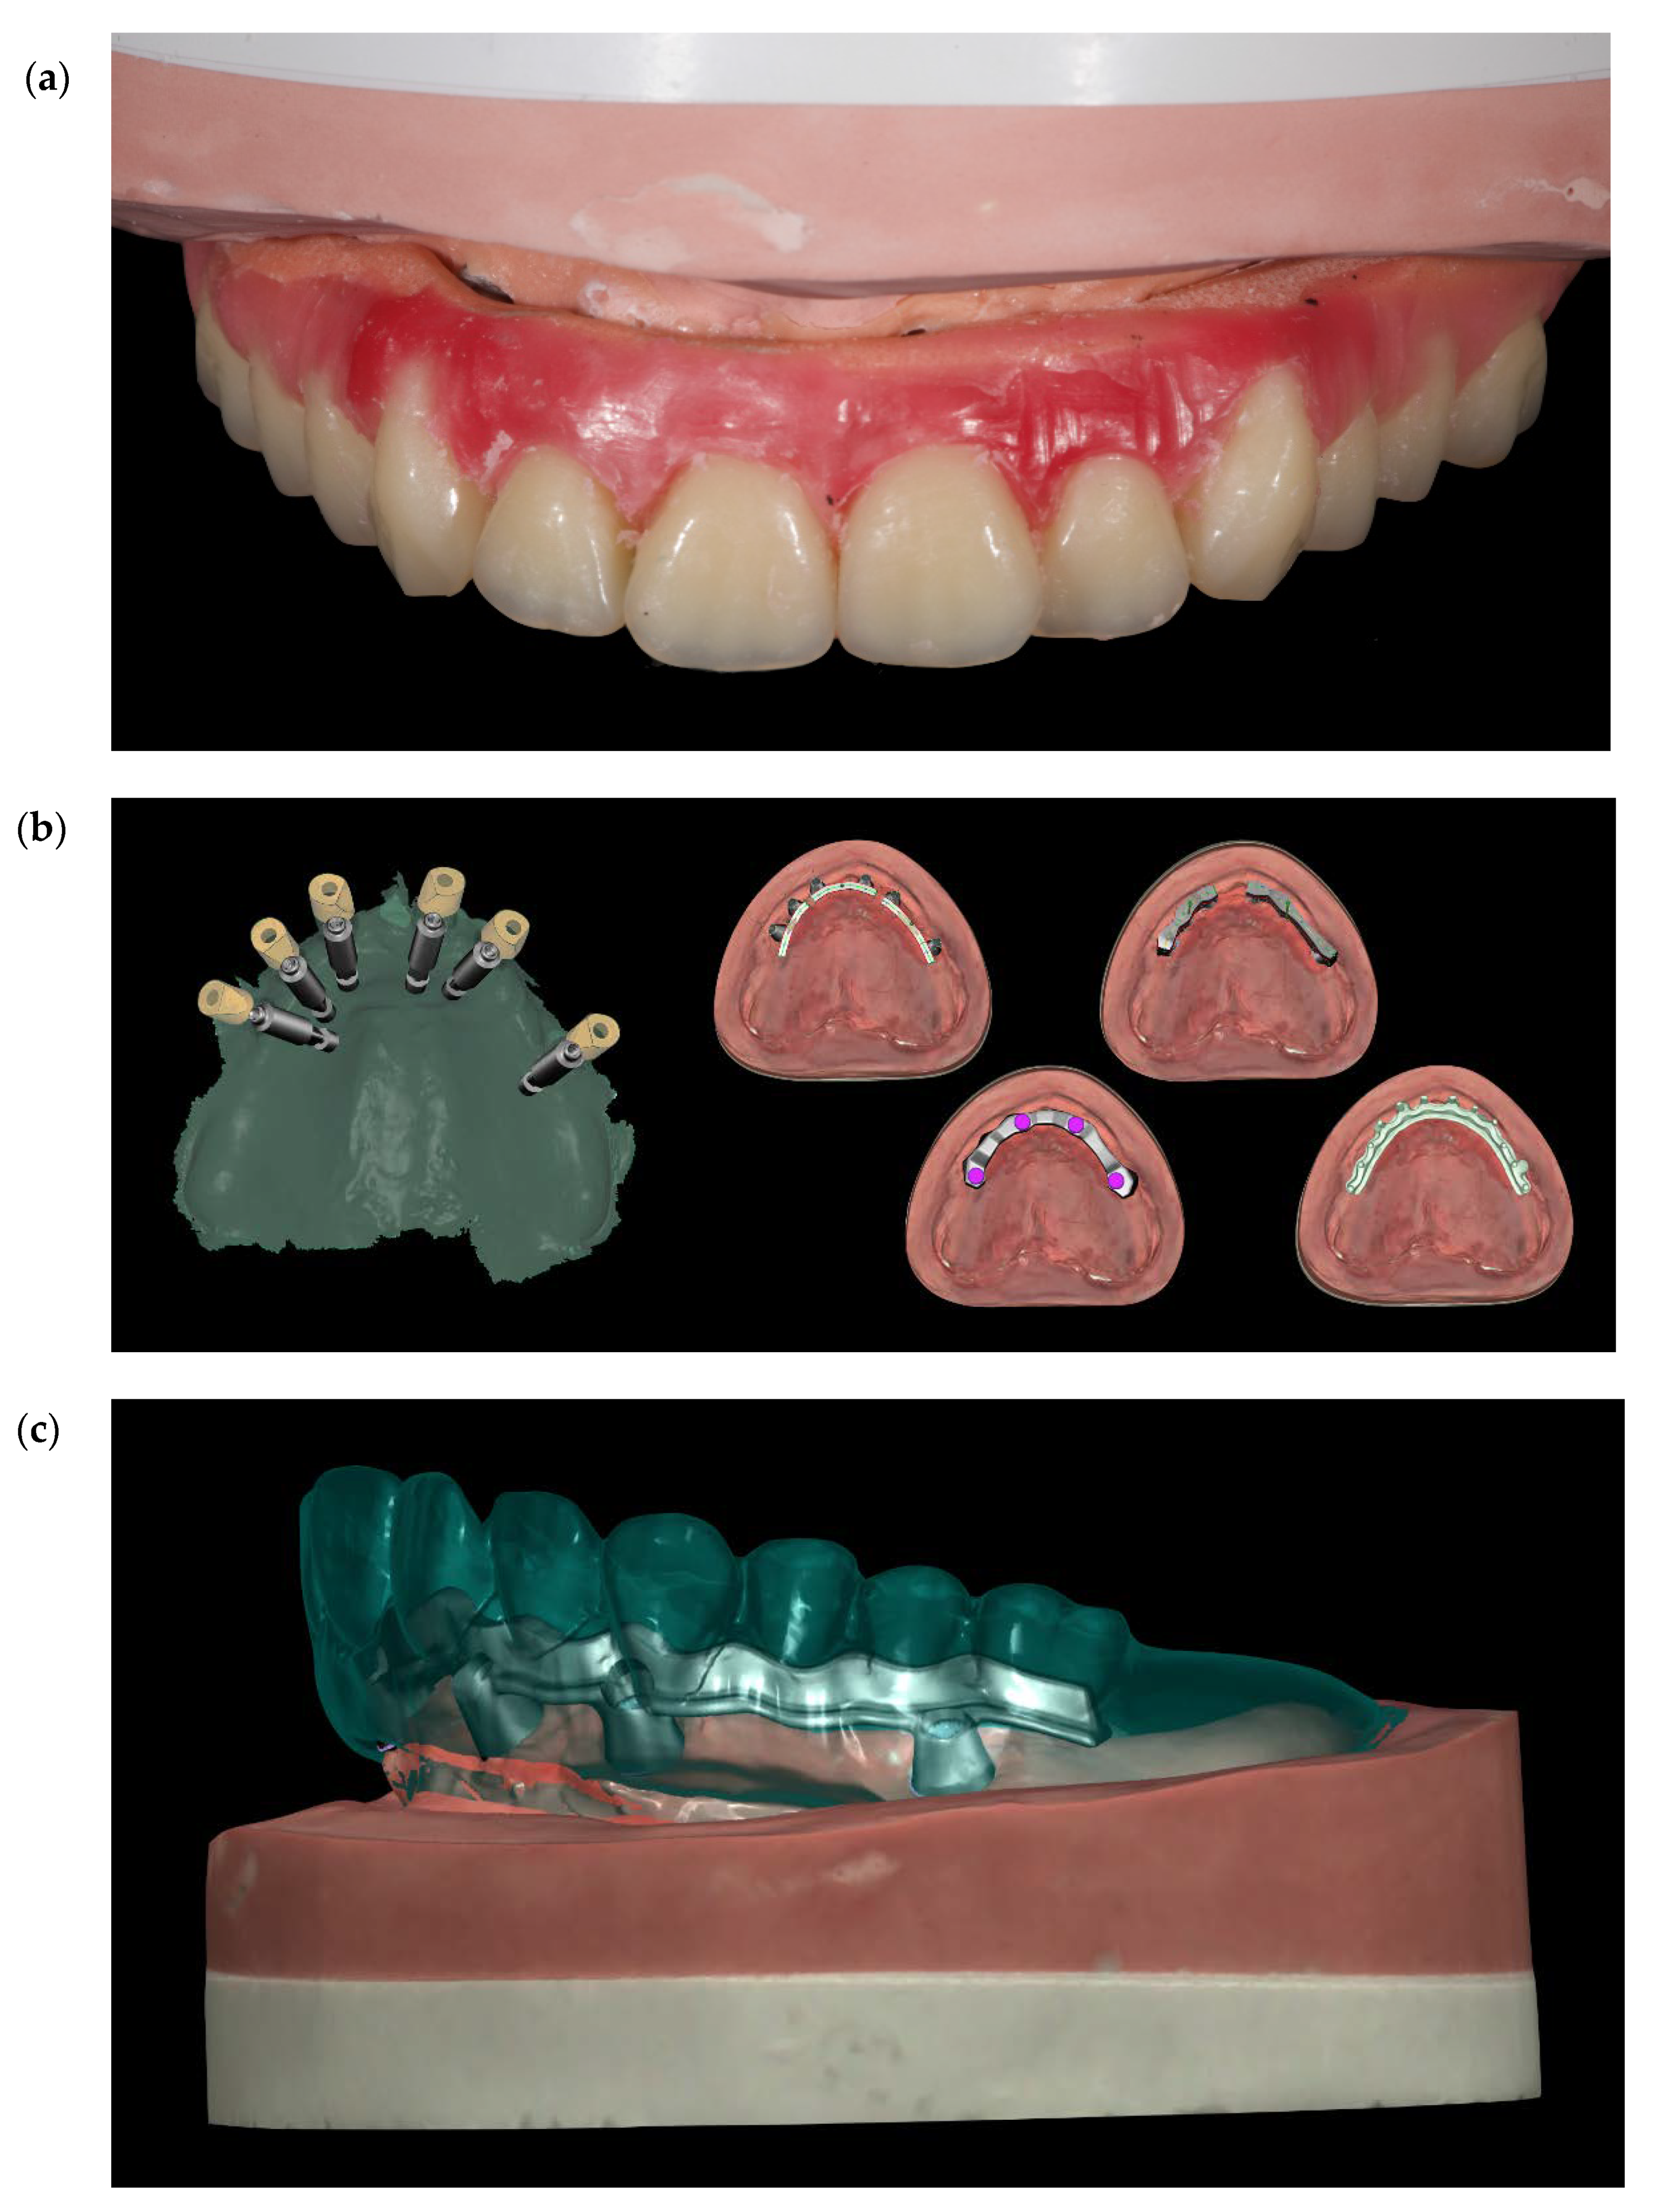

Figure 11.

(a) Set-up of the teeth. (b) Four different CAD projects (c) Single frame titanium bar CAD project.

Before definitive impression, multi-unit abutments were unscrewed, the implant connections were cleaned, and six OT Equator Titanium Abutments (Rhein’83, Bologna, Italy) with TiN coating were screwed (Figure 6), according to the manufacturer. Immediately after, the patient received a digital impression (CS 3600 intraoral scanner, Carestream Dental, Milan, Italy), taken at abutment level (Figure 7), using dedicated scan abutments (OT Equator Titanium Scan Abutment, Rhein’83). However, overlapping of the captured images failed to produce an accurate impression, maybe due to the disparallelism of the implant ranging from 65° to 86°. Hence, a prototype model was created and a convention gypsum impression [16] with a customized impression tray was taken at abutment level using conventional impression coping (Titanium Impression Coping, Rhein’83; Figure 8 and Figure 9). Esthetics, phonetics, the occlusal vertical dimension, and the centric relation were verified and approved by both the clinician and the patient (Figure 10 and Figure 11). Only after that, a definitive cast, implant position, and esthetic try-in were digitalized and a CAD/CAM titanium bar (NewAncorvis, Bologna, Italy) was anatomically designed with a dedicated software (Exocad DentalCAD, Exocad, Darmstadt, Germany) by a certified dental technician (MA), according to the prosthetic contours and the implant position. Three projects were created with a three-, two-, or one-piece CAD/CAM titanium bar, respectively (Figure 11b). Each of these projects failed to create an accurate titanium bar able to respect the minimum restorative space required by the prosthetic volume of the tried prosthesis, due to the multiple components involved (attachment system, prosthetic framework, artificial acrylic composite teeth, and pink acrylic base). Hence, a fourth project was created with a CAD/CAM titanium bar designed for a fixed screw-retained restoration, initially excluded due to the implant disparallelism. In order to overcome the undercuts created by the tilted implants, and to produce a passive-fit CAD/CAM titanium bar, abutments with an extragrade system were applied (Figure 11c). Extragrade is a special titanium abutment which has the possibility of entering, even in cases of strong disparallelisms, thanks to its internal design. On a large number of implants (those positioned worse from the point of view of the emergence profile), we cannot put the through screw. In this case, the abutment will be retained by the white Seeger only. The number of abutments without screws was limited to two, according to the manufacturer and considering the overall number of placed implants. Moreover, an angulated screw channel concept was applied to avoid the access hole in the vestibular area of the anterior teeth, moving the access holes in the pink area of the hybrid prosthesis. The fit of the implant bar was clinically and radiographically tested in the patient’s mouth, according to established criteria ([17,18,19]; Figure 12). It was important to position the flat surfaces of the abutment-bar connections in correspondence with the undercut created by the inclination of the implant; the flat surface indicates the location of the extragrade bevel, which allows the framework to overcome the undercuts created by the tilted implants. After that, an interocclusal record was taken in centric relation, and the prosthesis was delivered. The screw-retained fixed complete implant-supported prosthesis was seated in the patient’s mouth using the snap-on function offered served by the Seeger System (Figure 13). Four out of six screws were tightened according to the manufacturer, and the screw-holes were closed using composite pink materials. Finally, the occlusion was adjusted and radiographs were taken. The patient was scheduled for hygiene maintenance and control every 4 months (Figure 14, Figure 15 and Figure 16).